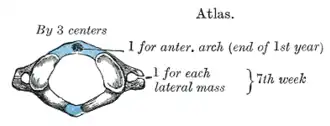

L'atlas s'ossifie à partir de trois points : un pour l'arc antérieur et un pour chaque masse latérale.

Les deux points d'ossification des masses latérales apparaissent à la septième semaine de grossesse.

À la naissance l'arc antérieur est encore cartilagineux et son point d'ossification apparaît à l'âge de 1 an.